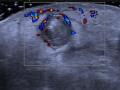

A ausência de trombo pode ser confirmada pela detecção de fluxo na veia femoral comum pelo Doppler Colorido (Figura 4).

Figura 4 - "Corte do Mickey" no modo Doppler colorido.